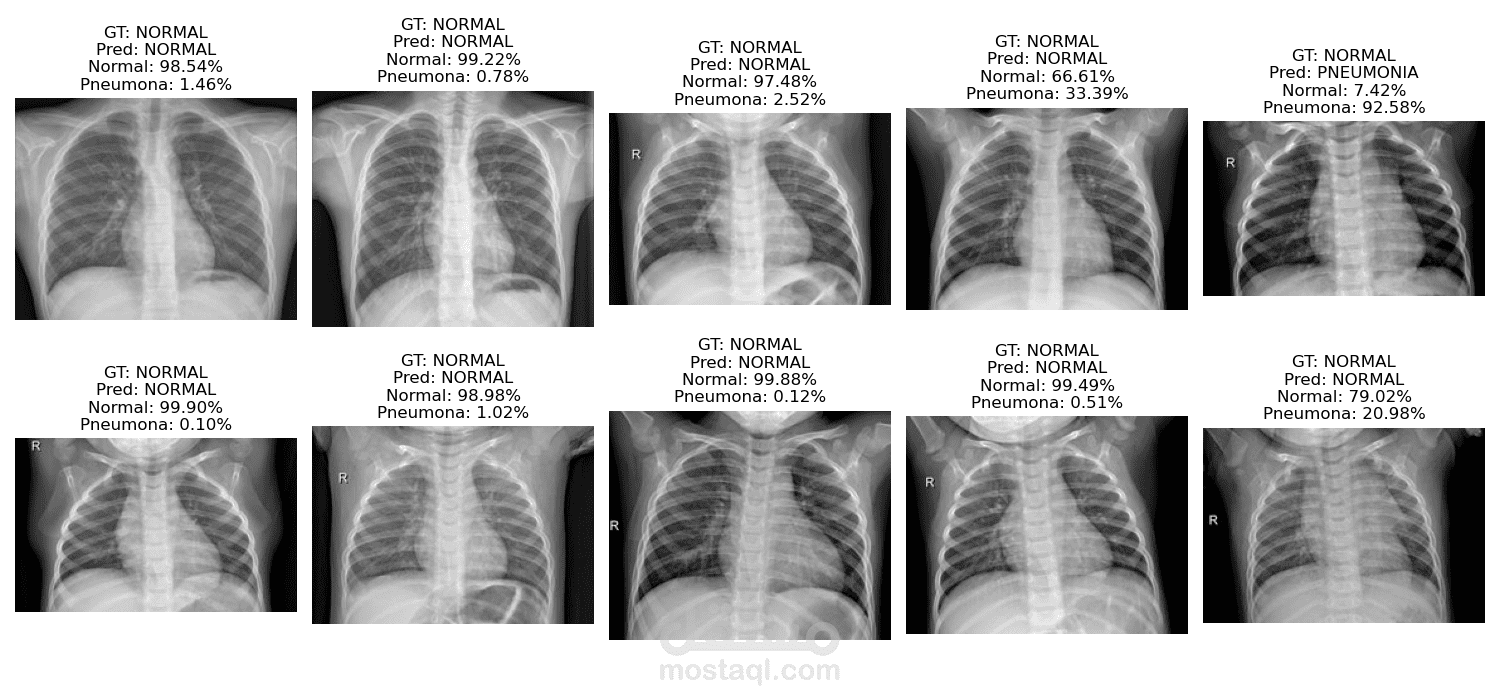

طورت نظام تصوير طبي متكامل مدعوم بالذكاء الاصطناعي، قادر على الكشف التلقائي عن الالتهاب الرئوي من صور الأشعة السينية للصدر. صُممت شبكة عصبية التفافية (CNN) مخصصة، ودُرّبت من الصفر باستخدام PyTorch، مع مراعاة عدم توازن البيانات، وتوسيع نطاقها، وجدولة معدل التعلم لتحقيق الأداء الأمثل. نُشر النموذج كتطبيق ويب Flask متكامل الوظائف، حيث يمكن للمستخدمين تحميل صورة أشعة سينية والحصول فورًا على تشخيص مع درجة ثقة. أداة عملية للعيادات ومقدمي الرعاية الصحية الراغبين في دعم أخصائيي الأشعة من خلال الفحص بمساعدة الذكاء الاصطناعي.